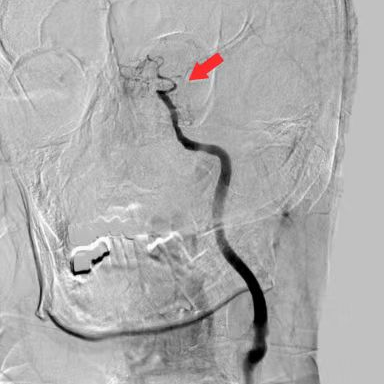

术前DSA

什么叫桡鞘【例久弥新】寻道于桡——瑞康通5.5F Introsky X导管鞘经桡取栓一例_https://www.jmylbn.com_新闻资讯_第8张

什么叫桡鞘【例久弥新】寻道于桡——瑞康通5.5F Introsky X导管鞘经桡取栓一例_https://www.jmylbn.com_新闻资讯_第9张

什么叫桡鞘【例久弥新】寻道于桡——瑞康通5.5F Introsky X导管鞘经桡取栓一例_https://www.jmylbn.com_新闻资讯_第10张

什么叫桡鞘【例久弥新】寻道于桡——瑞康通5.5F Introsky X导管鞘经桡取栓一例_https://www.jmylbn.com_新闻资讯_第11张

什么叫桡鞘【例久弥新】寻道于桡——瑞康通5.5F Introsky X导管鞘经桡取栓一例_https://www.jmylbn.com_新闻资讯_第12张